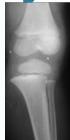

Case Example: 12-year-old male, Salter-Harris Type II